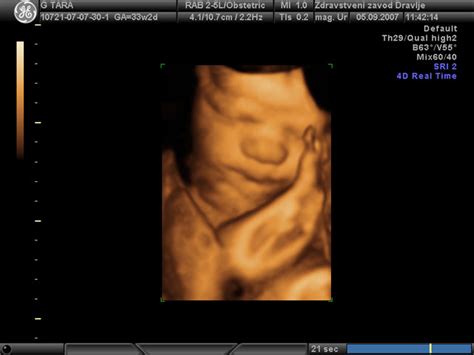

Čeprav 3D ali 4D ultrazvok nimata pri nobeni drugi bolezni v nosečnosti pomembnejše vloge, pa merjenje pretoka krvi skozi krvne žile maternice med 20. in 24. tednom nosečnosti lahko v večini primerov napove pojav kasnejše gestoze. Pri vseh nekoliko težjih oblikah zapletov je potrebna nujna hospitalizacija in intenziven nadzor. Zdravljenje se določi na podlagi izvidov, stanja nosečnice in gestacijske starosti.